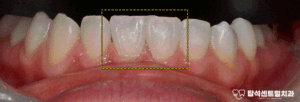

민락동 치과 치아 사이 벌어짐 원인 분석하고 무삭제 라미네이트 치료 하는 과정 소개

안녕하세요민락동 치과 입니다.벌어진 앞니 사이 공간이 있다면자연스럽게 눈길이 가게 됩니다. 특히 아랫니가 벌어져 있으면웃을 때 더욱 눈에 띄어고민이 깊어지는 경우가 많습니다.앞니가 벌어져 보이는 이유는여러가지가 있습니다. 선천적으로 치아 크기가 작거나 턱…